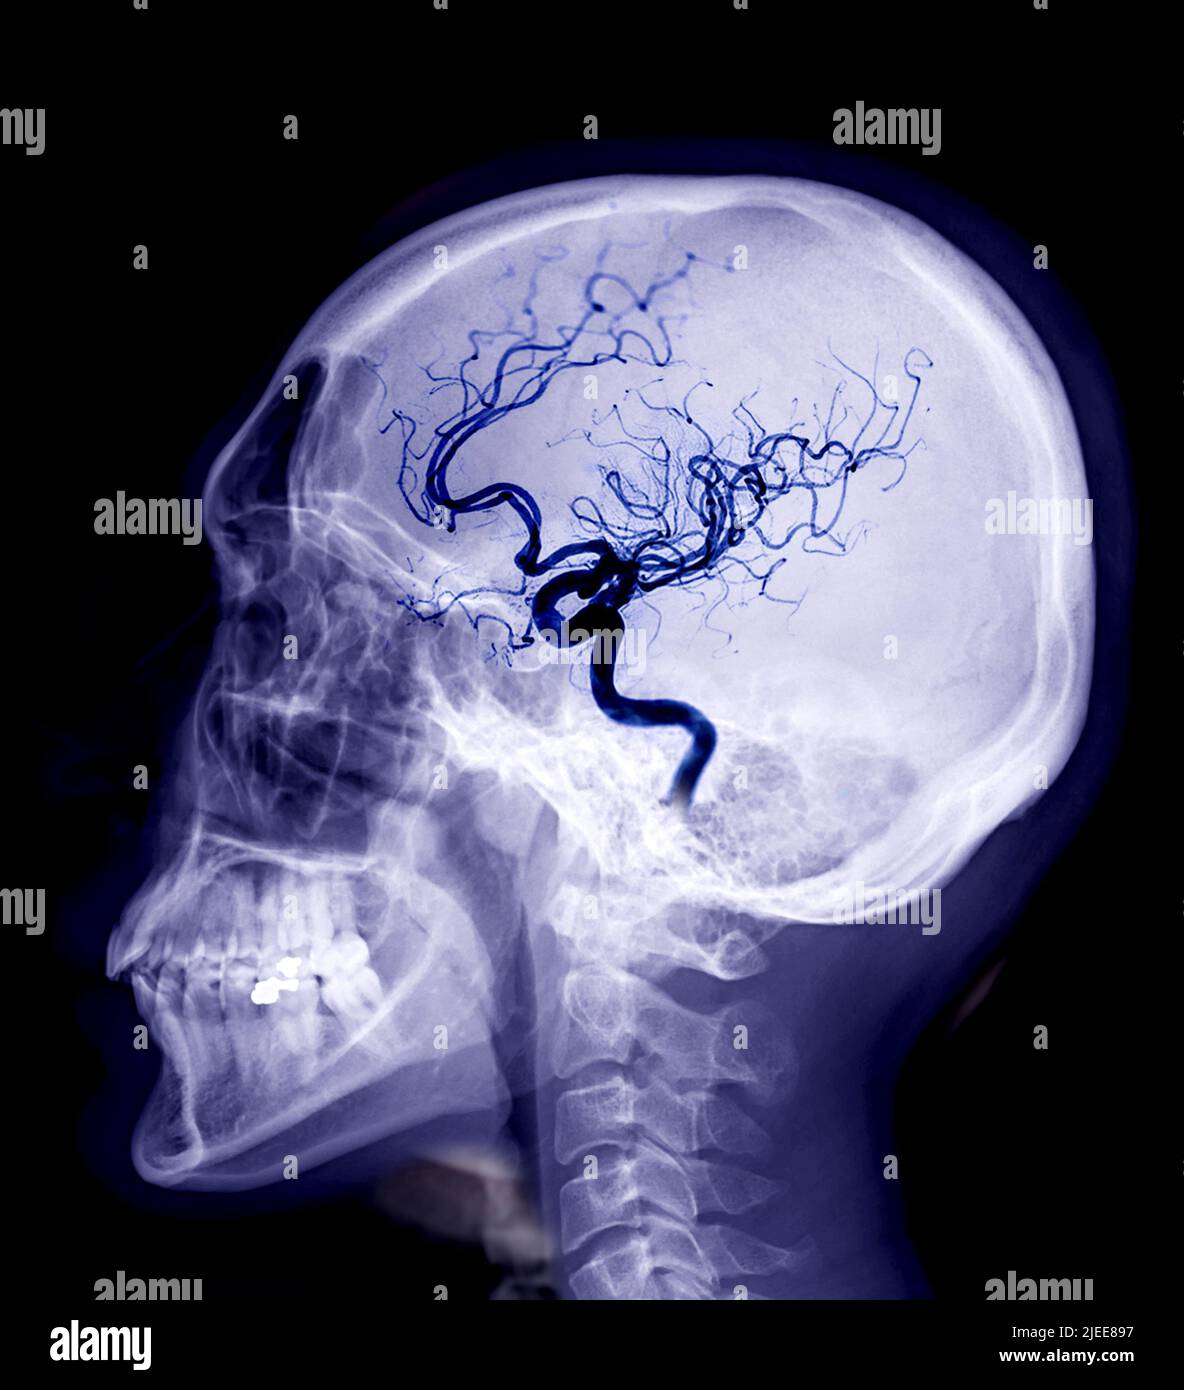

Schädel-Röntgenbild der lateralen Ansicht des Menschen mit zerebralem Angiogramm isoliert auf schwarzem Hintergrund.